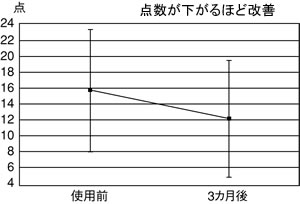

| 図3 トリゴネコーヒーの認知症予防効果(エーダス検査) |

|

2つ目はコーヒーです。コーヒーにはカフェイン以外にトリゴネリンという成分があり、抗認知症作用があります。インスタントではなく、焙煎したものでなければいけません。

トリゴネンは、豆の種類や入れ方でも量が変わるので、米子市の澤井珈琲が、誰が入れてもトリゴネンが高濃度に入った「トリゴネコーヒー」をつくりました。ティーパックに入っていて、通信販売もしています。

私たちもこのコーヒーを試してみました。昨年度、予防教室で約30人に飲んでもらい、エーダス検査をしたところ、点数が改善しました(図3)。これも新しい予防法になる可能性を持っていると見ています。